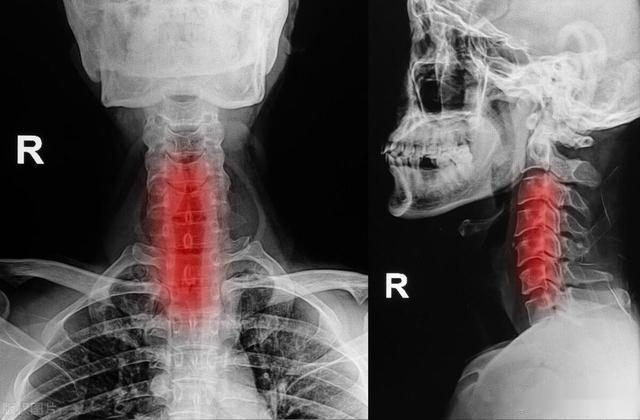

经过医生的详细检查,杨先生被诊断为颈椎病引起的手麻。医生告诉他,颈椎病导致手麻的原因主要有三个:颈椎间盘突出压迫神经根、颈椎骨质增生刺激周围神经以及颈椎肌肉紧张导致神经受压。杨先生的案例提醒我们,手麻并非小事,它可能隐藏着更严重的健康问题。

如果手经常出现麻木,那70%可能是因颈椎病造成。

当颈椎间盘退行性变、颈椎骨质增生等原因导致颈部神经根或脊髓受压时,患者就会出现手麻、手指无力、颈痛等症状。这些症状可能在特定姿势下加重,如低头、抬头或转动头部时。颈椎病还可能伴随其他症状,如颈肩部疼痛、头晕、恶心等,影响患者日常生活。

因此,颈椎病患者应及时就医诊治,生活中多加强颈部锻炼、调整工作习惯、使用合适高度的枕头,能有效缓解手麻,保护颈椎。